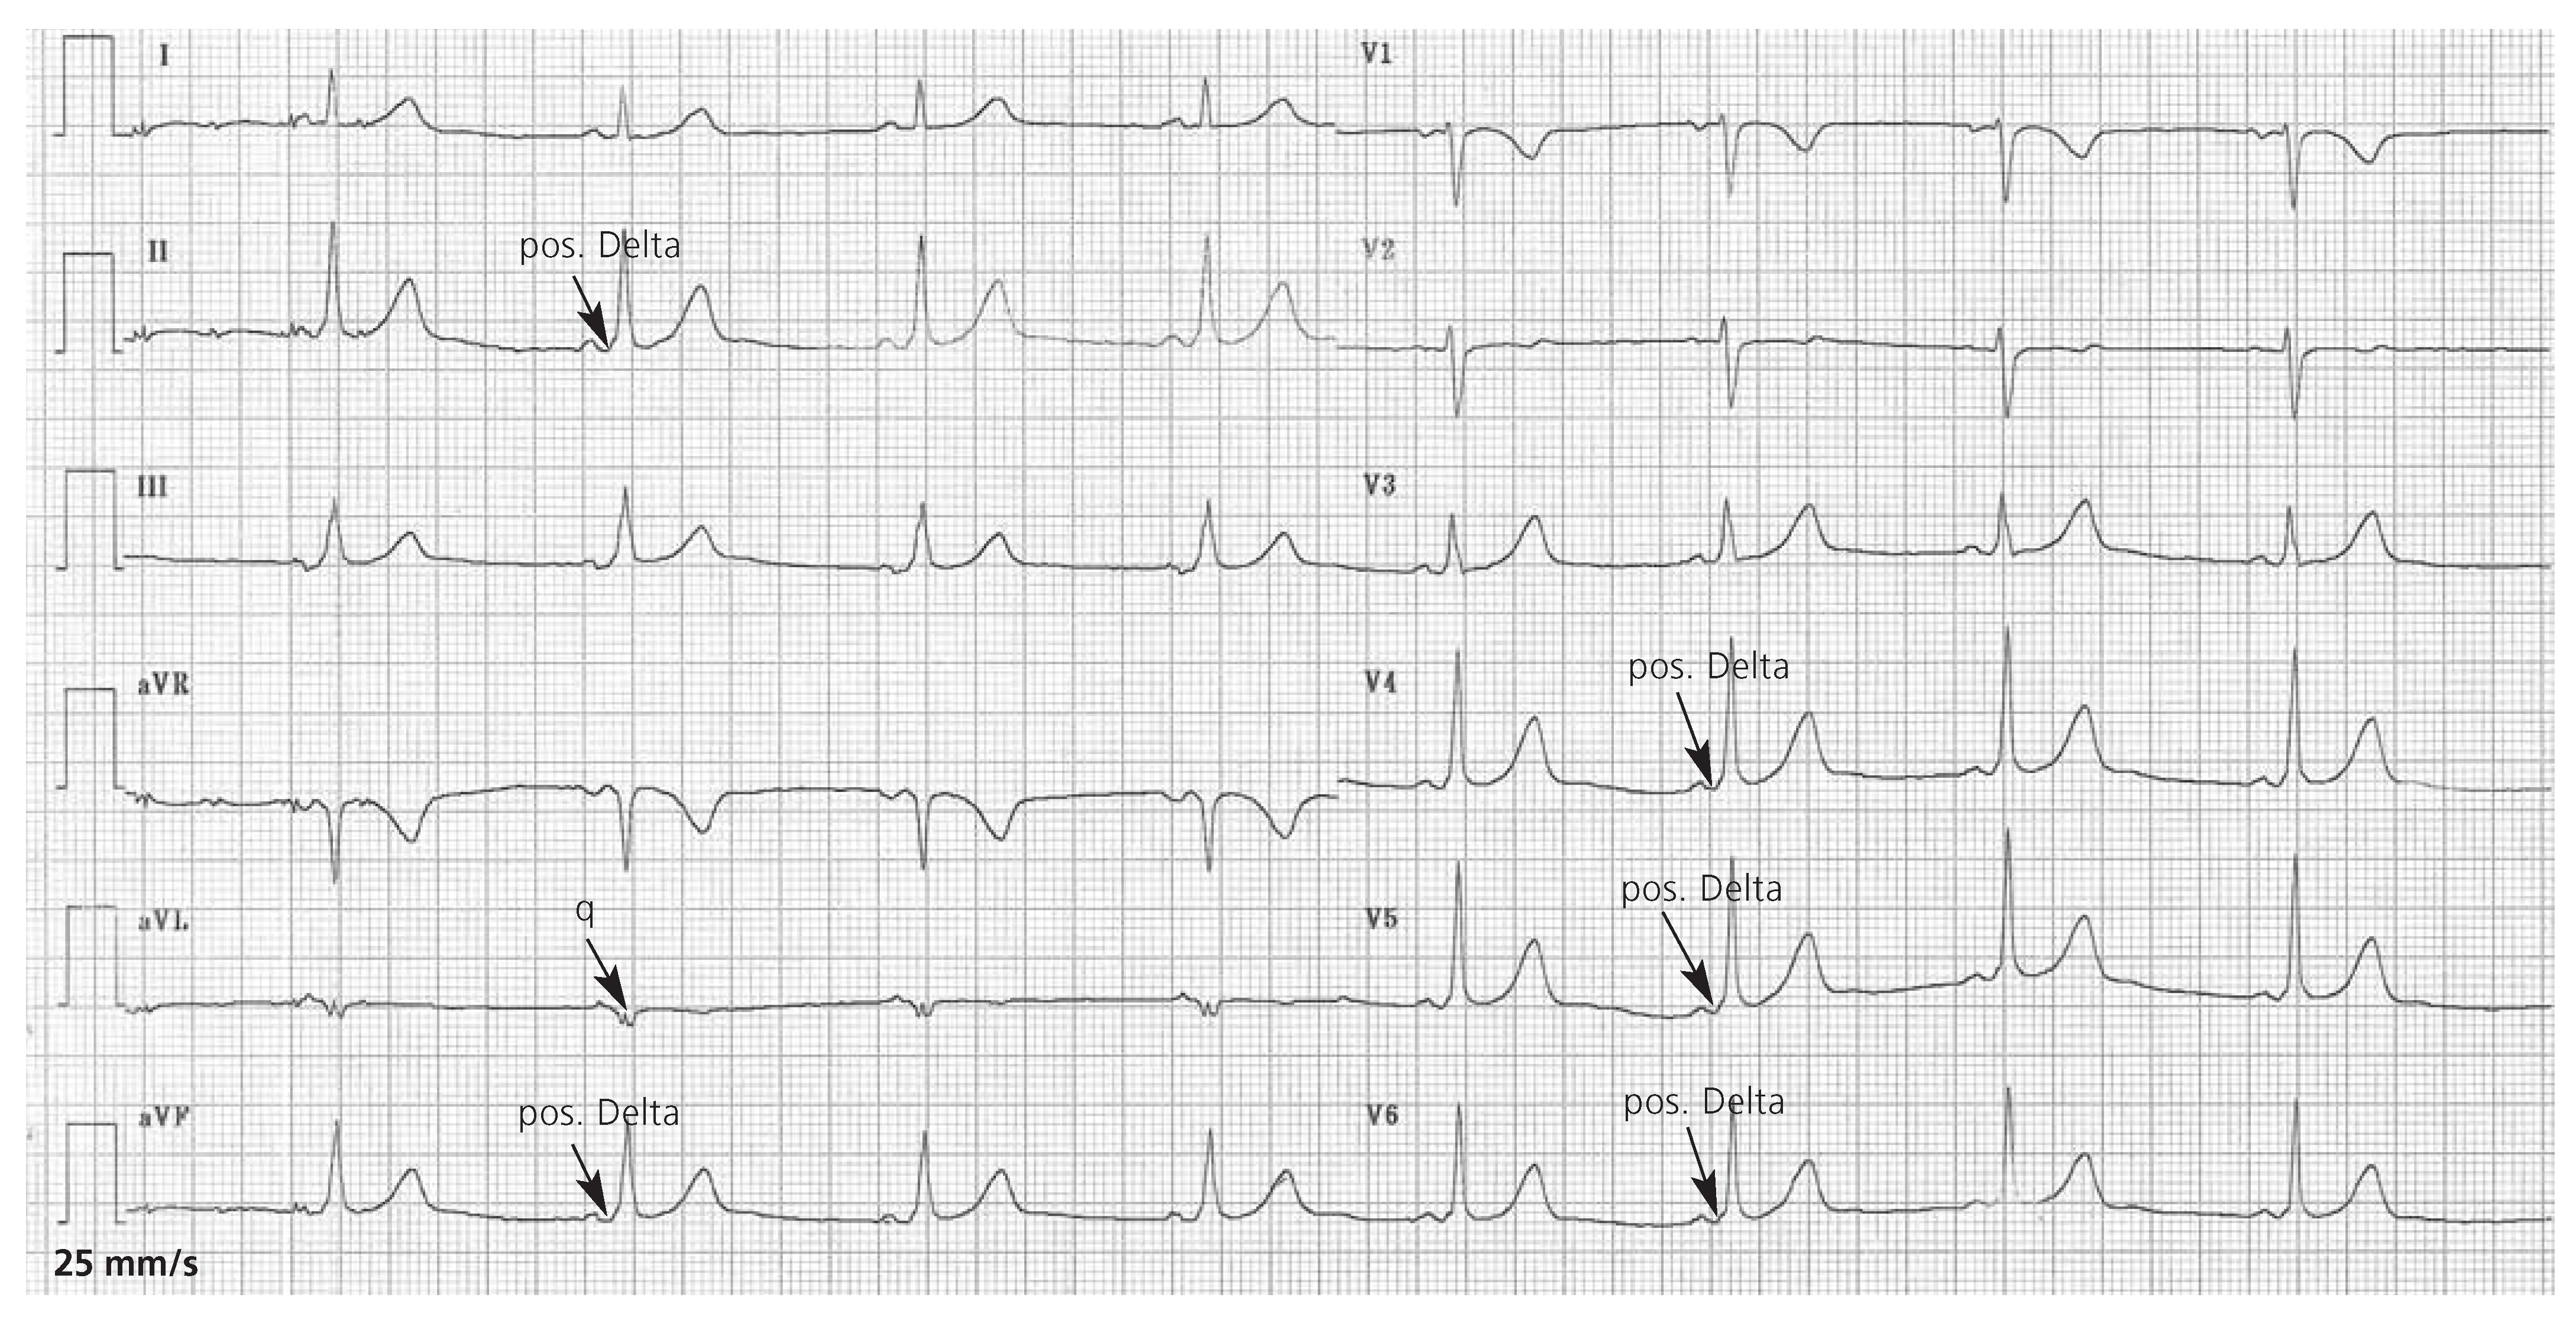

Therapie der Wahl ist die rasche Elektrokonversion. Nach Applikation von 200 Joule stellt sich prompt ein normofrequenter Sinusrhythmus ein. Das Kontroll-EKG (Figure 2) zeigt einen normokarden Sinusrhythmus und eine verkürzte PQ-Zeit (100 ms) mit positiver Delta-Welle in II, III, aVF, V2–V6, isoelektrischem Delta in V1 und q in aVL. Zu vermuten ist ein linkslaterales Bündel [2].

Figure 2.

Das 12-Kanal-EKG nach Elektrokonversion zeigt einen normokarden Sinusrhythmus und eine verkürzte PQ-Zeit (100 ms) mit positiver Delta-Welle in II, III, aVF, V2–V6, isoelektrischem Delta in V1 und q in aVL.